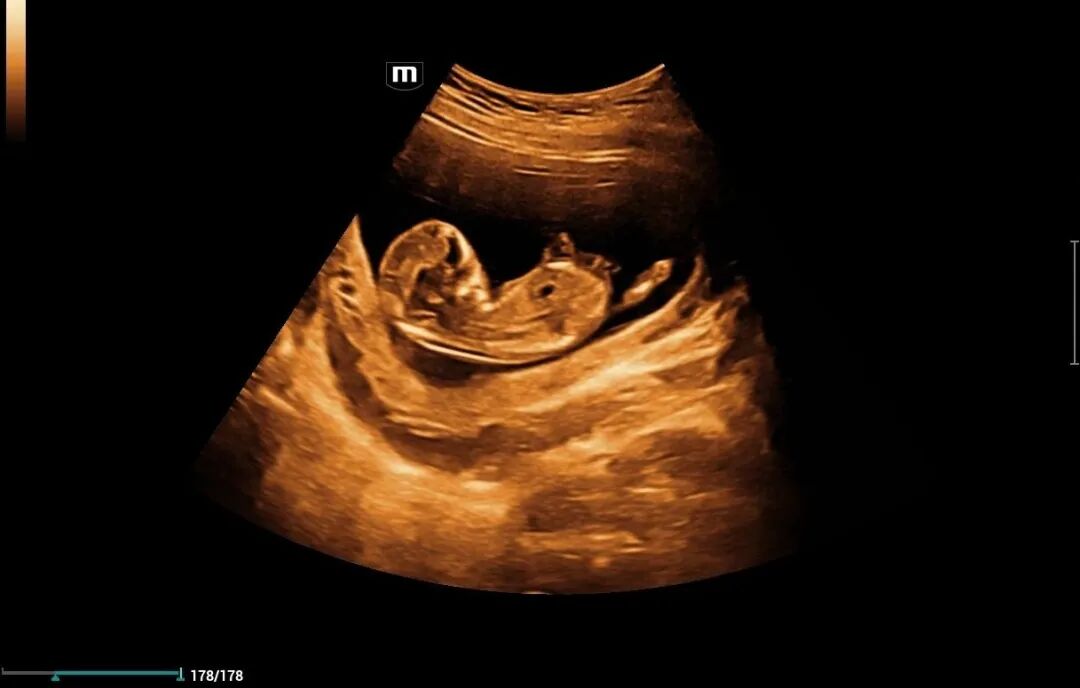

为进一步提高我院诊疗检查与诊断水平,不断满足城乡患者日益增长的就医需求,健全和完善医疗保障体系。2022年12月我院引进了mindray- Resonal9T高端彩色多普勒超声系统正式投入使用,此设备具备超声介入、超声造影、超声高帧率 STE 剪切波弹性成像及应变式弹性成像(甲状腺、乳腺、肝脏),二维、三维、四维、阴式、盆底、心脏及血管超声等功能。此设备的引进标志着海伦影像学科将跨越新的高度,以此助力城乡百姓解决看病难,看病贵的就医难题!

5.妇科疾病。如子宫肌瘤、子宫内膜病变、卵巢疾病,异位妊娠、盆腔疾病等。